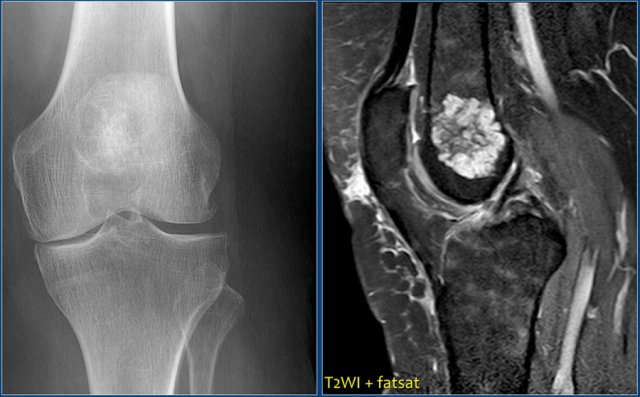

Chondroblastoma (2)

There is a well-defined lytic lesion located posteriorly in the proximal epiphysis of the tibia.

On the radiograph there is some reactive sclerosis surrounding the lesion.

There is no matrix formation.

On the coronal T2-weighted image with fat suppression the lesion has a high SI and subtle internal ridges.

There is edema of the entire epiphysis.

On a sagittal T1-weighted image there is a discrete sclerotic margin.

If there were signs of osteoarthrosis, the differential diagnosis would be a chondroblastoma and a degenerative cyst (or geode).